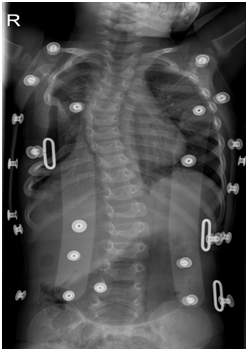

Follow-up MRI of the thorax performed two months later did not reveal any relapse of the mass. Thoracic scoliosis was seen on the AP plain film of the spine on the 4-month follow-up. The paradoxical respiration has resolved Figure 5. On the 6th month follow-up an appropriate scoliosis bandage was prescribed by the orthopedic surgeon Figure 6. Currently the baby is on orthopedic follow up for her scoliosis repair.

Figure 5 Plain radiogram 2 months later. Note the ipsilateral scoliosis.

Figure 6 Plain radiogram 6 months later. The vertebral column is supported by appropriate bandage.

Scoliosis of the thoracic vertebral column seems to be an inevitable late complication16. The grade of scoliosis and the decision to cure it, depends on the extension of the lesion and the number of the ribs affected. Scoliosis may present in young patients after just a plain thoracotomy for various interventions such as esophageal atresia repair, lobectomy or sequestration excision. Is obvious that the ablation of ribs and therefore the bereavement of the static support of the vertebral column leads to a grade of scoliosis. Confrontation depends on the grade of columnar deviation, the age and the provoked clinical problems.17,18 Orthopedic surgeons, neurologists and pneumonologists must collaborate to decide the need of surgical repair.